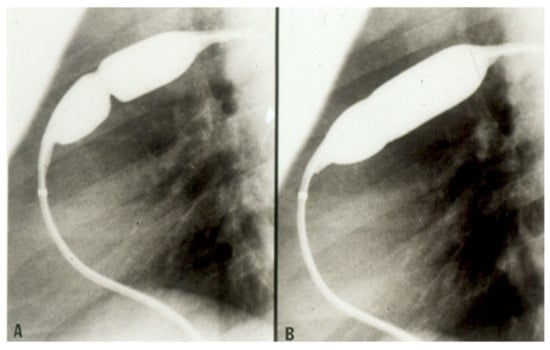

- Rao, P.S. Balloon aortic valvuloplasty: A review. Clin. Cardiol. 1990, 13, 458–466. [Google Scholar] [CrossRef] [PubMed]

- Rao, P.S. Balloon aortic valvuloplasty. J. Interv. Cardiol. 1998, 11, 319–329. [Google Scholar] [CrossRef]

- Agu, N.C.; Rao, P.S. Balloon aortic valvuloplasty. Pediatr. Ther. 2012, 5, 004. [Google Scholar] [CrossRef]